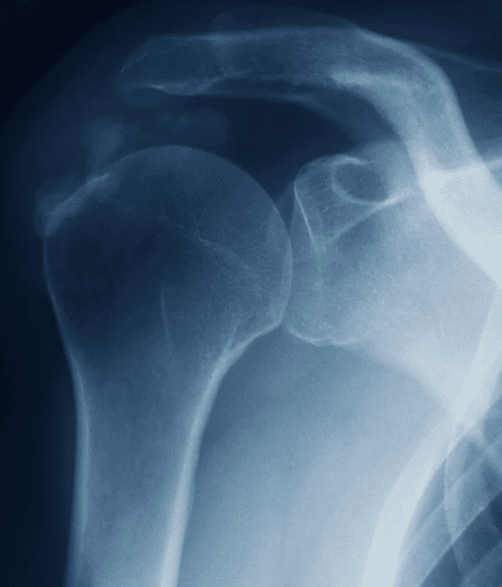

El hombro es una de las articulaciones más móviles del cuerpo humano. Gracias a él podemos levantar los brazos, girar, empujar y realizar cientos de movimientos diarios. Pero justamente esa movilidad lo hace vulnerable a lesiones, siendo la tendinitis una de las más comunes.

Se trata de una inflamación de los tendones que rodean la articulación, y que puede afectar tanto a deportistas como a trabajadores manuales o personas que realizan movimientos repetitivos en su día a día. Aunque al inicio parece un dolor pasajero, si no se trata a tiempo puede transformarse en una molestia crónica y limitante.